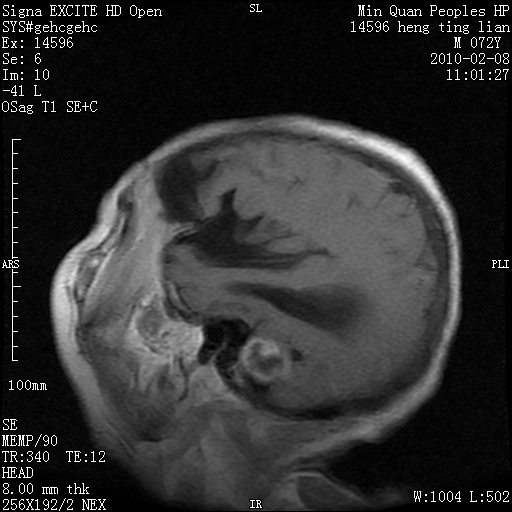

m,72,头疼,头晕两年,伴视力模糊三月,饮食呛咳两天。pe:颈部抵抗,左眼突出,左眼瞳孔约3mm,对光反射消失,双眼失明,伸舌困难,双肺呼吸音粗,心率110次/分,左上肢肌力i级,左下肢屈曲,肌张力高。现有08年2月19mri平扫及10年2月8日mri增强请会诊。ct病灶呈低密度伴散在点、片状等密度区,无明确钙化(无ct片资料可供上传)。[

脑外肿瘤,囊实性,环状不规则强化,内听道扩大,考虑神经源性肿瘤

左侧桥小脑区占位伴梗阻性脑积水----考虑 1神经鞘瘤 2室管膜瘤。

左侧桥小脑区神经鞘瘤伴梗阻性脑积水。

脑外肿瘤,病灶呈匍匐蔓延,表皮样囊肿可能性大。